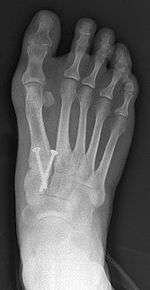

Syndesmosis procedure addresses specifically the two fundamental problems of metatarsus primus varus deformity that gives rise to the bunion deformity. They are leaning and instability of the first metatarsal bone . Syndesmosis procedure uprights the leaning first metatarsal bone with strong binding sutures between it and the second metatarsal bone (Fig. 2) and then also stabilizes it uniquely by creating a fibrous connecting bridge between these two bones (Fig. 3,4). First metatarsal bone can be readily realigned is because by definition of the metatarsus primus varus deformity its first metatarsal is abnormally loose and mobile.